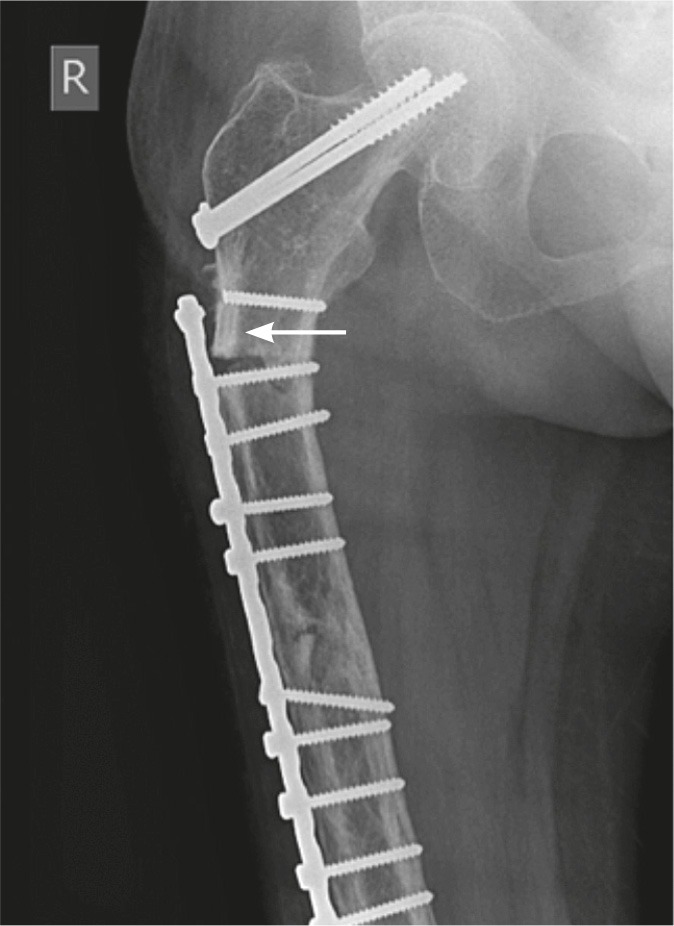

Figure 3.

Patient 3. Fracture through the penultimate screw hole. The proximal screw had fractured earlier, leaving it uninvolved in the tension-band construct. The patient also had previous cancellous screw insertion. Lateral cortical thickening is evident (arrow).

In 8 of the injuries, the fracture line was at or just beyond the tip of the plate (Figure 2). In 3 of the injuries, the fracture was sustained through the second-most proximal screw hole of a plate. In 2 of these cases, the penultimate screw hole was the last functioning screw hole at the end of the plate (Figure 3). The fractures showed some radiographic features of atypicality such as (1) thickening of the lateral femoral cortex, (2) simple transverse or short oblique fracture pattern, and (3) absence of comminution.